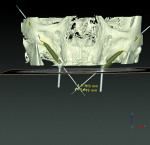

Pretreatment planning with planning software (NobelClinician, Nobel Biocare) was accomplished prior to zygomatic surgical protocols (Figure 10). Figure 11 demonstrates the sagittal view of the presurgical treatment planning processes and the volume of the patient's right zygomatic arch, along with the planned positioning of the 45 mm zygomatic implant spatially to deliver the coronal aspect of the implant in the correct position of the arch to minimize prosthetic thickness of the interim definitive prosthesis. The patient was scheduled for maxillary revision surgery and placement of single zygomatic implants bilaterally, with evaluation of the remaining implants for either continued use or removal.